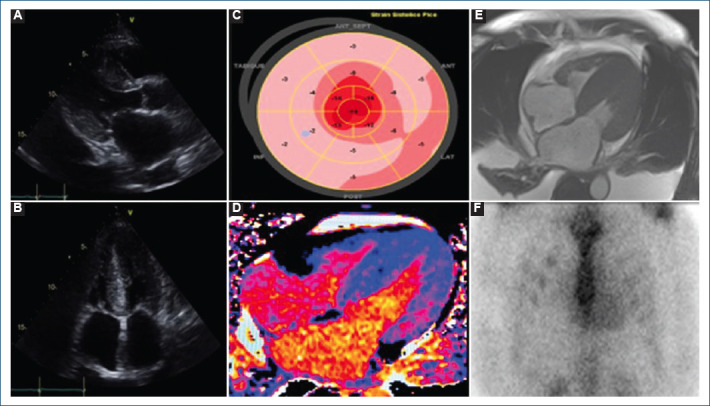

Multimodality imaging approach in light chain (AL) cardiac amyloidosis: a case report.